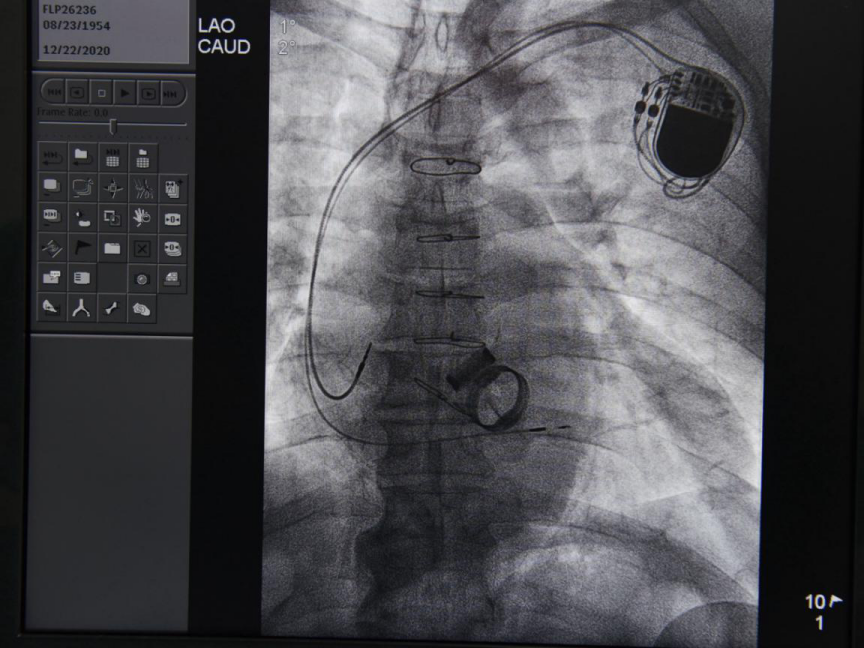

手术中

永久性心脏起搏器是治疗各种原因引起心动过缓和传导功能障碍性疾病的主要方法,常用的心房心室起搏不可避免改变了心脏的收缩顺序,对心功能造成一定影响,尤其是心功能不全的患者影响更大,希氏束起搏是使特制的3830电极导线通过特殊形状鞘送入右心室室间隔面,在心内电生理图的定位下旋入到左束起搏,起搏时心电向量与自身心律相同,QRS波无增宽,Vp-Ⅴ间期等于H-V间期,心肌收缩的顺序更接近正常心肌顺序,能更好地保护心功能。而希氏束起搏相对于传统起搏器起搏,除了可以改善传统房室传导阻滞者心率,缓解头晕、晕厥等症状,还可以改善传导阻滞及缓慢型房颤伴心功能不全患者心功能情况;目前大量循证依据提示希氏束起搏患者心脏射血分数与昂贵的心脏同步化治疗(CRT/CRTD)相仿,可做CRT双心室起搏的替代方案,同时减少医疗费用。

术后